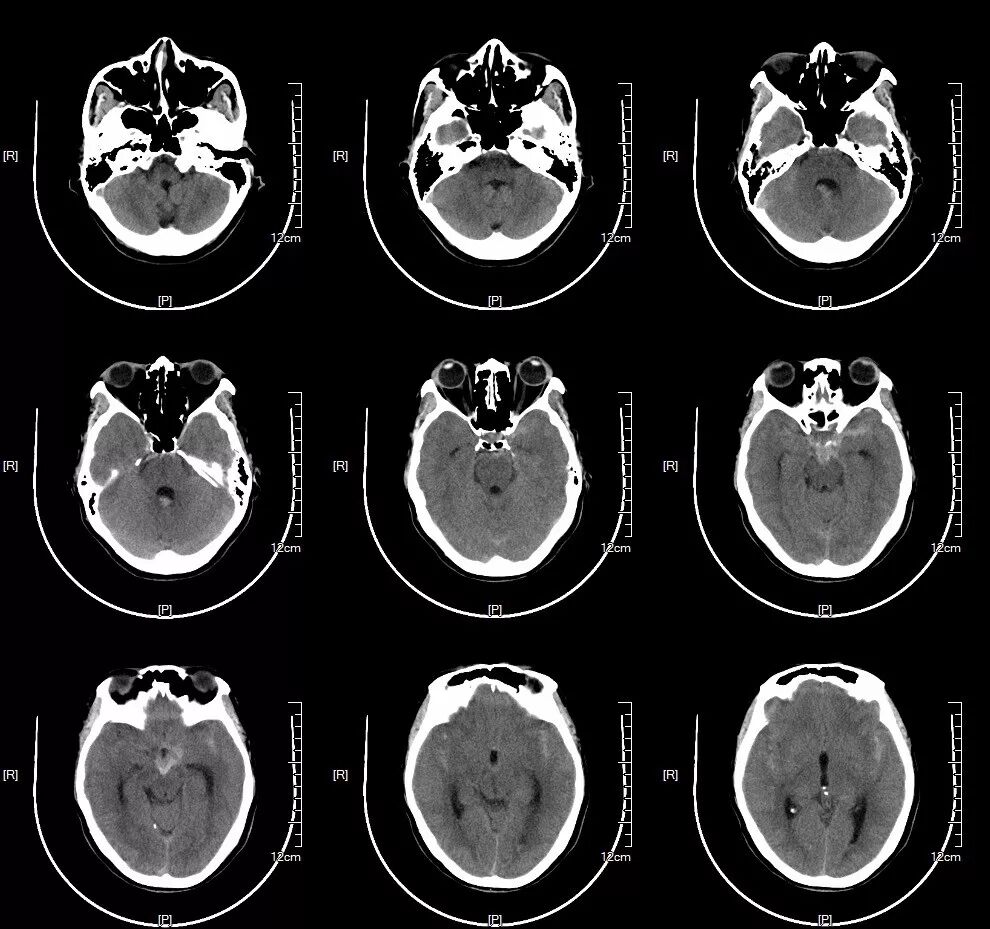

术前CT:鞍上池及双侧外侧裂见高密度影,蛛网膜下腔出血。(图1)

术前CTA:基底动脉顶端见瘤样突起,大小约0.5×0.8cm;余血管无明显异常。(图2)

图3-1. 患者入院后头颅CT提示蛛网膜下腔出血,以脑干前方为主,提示后循环动脉瘤破裂出血可能。

图3-2. 患者入院后头颅CTA提示基底动脉顶端动脉瘤,大小约0.5×0.8cm。余血管未见明显异常。